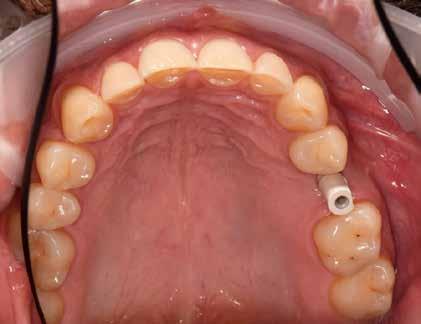

A laboratóriumokban és a fogorvosi rendelőkben mindenki ismeri ezt az esettípust: a páciensnek generalizált parodontitis miatt már több foga is elveszett a felső állcsontban, és kivehető fogsort visel. A tömörebb mandibulacsont eddig jobban bírta a krónikus bakteriális fertőzést, egészen addig, amíg a metszőfog körüli csonthiány túl nagy lett, és a metszőfogat is ki kellett húzni. Ennek az egyetlen résnek köszönhetően a páciens fix restaurációt kért. Az implantátum nem volt kívánatos, és nem is javasolt a krónikus fertőzés, a rossz csontozat és a korlátozott hely miatt. A következő esetpéldában dr. Julio Gomez Paris (Rosario, Argentína), aki fogorvos és fogtechnikus egyben, bemutatja, hogyan lehet ez a fajta eset minimálisan invazív, esztétikus és gazdaságosan megoldható a fogszín szisztematikus és precíz, a VITA 3D-MASTER fogszínkulcs segítségével történő meghatározásával és a hozzáillő VITA YZ ST Multicolor cirkon anyagának használatával (VITA Zahnfabrik, Bad Säckingen Németország).

A fog eltávolítása és szisztematikus fogszínmeghatározás

A 76 éves páciens azért kereste fel a fogorvosi rendelőt, mert észrevette, hogy a 31-es fog kilazult, és az azzal való harapás fájdalmat okozott. Parodontális szondázás és röntgen diagnosztika után egyértelmű volt, hogy a fogat nem érdemes

4. ábra: A 32, 41 és 42 fogak előkészítése hídpillérekként.

megőrizni. Helyi érzéstelenítést követően a fogat eltávolítottuk, és a 42, 41, illetve 42 fogak között keletkezett foghiányt híd megoldással teveztük megoldani a gyógyulási folyamat után. A pontos fogszínmeghatározást és dokumentálást a VITA Linearguide 3D-MASTER segítségével végeztük el annak érdekében, hogy a megfelelő árnyalatú cirkontömböt tudjuk kiválasztani. A fogszínkulcs lehetővé teszi a szisztematikus és gyors fogszínmeghatározást két lépésben. Minden fogszín a világossági értékből, az árnyalatintenzitásból és a színárnyalatból tevődik össze. Emiatt a VITA Valueguide 3D-MASTER segítségével először csak a fogak világosságát, azaz fekete/fehér tulajdonságát állapítjuk meg. A 0-tól 5-ig

terjedő skálán a választás a 2-es árnyalatot mutató pálcára esett, tehát a VITA Chroma/Hueguide 3D Master 2-es csoportban folytattuk a meghatározást. A színárnyalattal (M) és az árnyalatintenzitással (3) kölcsönhatásban végül egy 2M3 fogszín került meghatározásra és fotódokumentálásra.